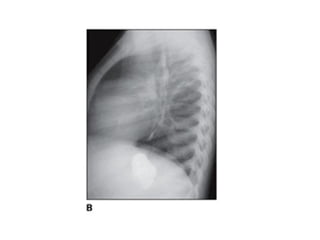

•3. Perfil: Usa-se perfil esquerdo para evitar magnificação do

coração. Sempre solicitada com a PA.

IDENTIFICAÇÃO DA RADIOGRAFIA

ESTRUTURAS MAIS

DEMONSTRADAS:

Pulmões, coração.

Usa-se o perfil com o

lado esquerdo próximo

do filme para evitar

que o coração seja

ampliado.